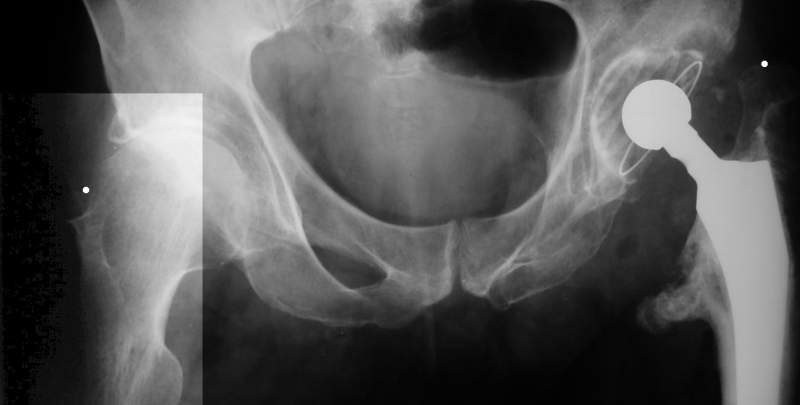

Насчет 8 см согласен с А.Н. Челноковым, это наверное ортопедическое за счет приводящей, сгибательной контрактуры и, возможно, колена. на ликвидацию укорочения у нас обычно уходит около 2-х нед. снимки в приложении, возможно не очень показательные, но других с ходу не нашел, завтра еще поищу.

Еще пара фото, ситуация несколько иная, задачи те же, открытое вправление застарелого вывиха в 2002, молодой возраст. Сейчас госпитализирована для эндопротезирования.

А за счет чего такое укорочение? По снимку не видно соответствующего дефекта. Ну плюс приводящая контрактура - но все равно как-то уж больно много. Может, сделать снимки и таза обзорный с обоими проксимальными отделами бедра, и коенный суставов с приложенной линейкой какой?

Судя по снимку, максимум истинное укорочение около 4 см, что может быть коррегировано интраоперационно. Вопрос в другом: куда ставить ацетабулярный компонент в истинную или во вновь сформированную ( впадина диспластичная).

Невозможно не согласиться с Анатолием, чтобы заниматься адекватным планированием как минимум прямая проекция таза должна быть сделана, как

The X ray that you provided does not show 8 cm of shortening. Perhaps you could send one showing the whole pelvis and proximal femurs.

I agree with Dr Eid's comments. The origin of the 8 cm leg length difference is a puzzle. Is this a clinical measurement? In that case contracture of the joint might affect the measurement. Can we see an AP pelvis to include both hip joints (including a calibration object with a known length) so that the difference in leg lengths that can be ascribed to the hip deformity and bony reabsorption can be measured. This sort of xray will help with templating for the TJR also. I would be very tempted to do a one stage procedure and accept some shortening. Shoe lifts should take care of a 3-4 cm difference.

До травмы проблем с ногой не было. Укорочения, болей и т.п. не отмечал. Сегодня перемерял укорочение - меньше 7 см намерять не

По уровню малых вертелов (с учетом рентгеновского увеличения) получается 5 см. Клинически ногу низвести путем тракции невозможно. Из движений - сгибание до 40*, остальные движения "символические".

Ортопедическое укорочение пострадавшей ноги может быть и 7, и 10 см. за счет контрактур в тазобедренном суставе, а вот истинное укорочение, судя по представленным рентгенограммам, вряд ли больше 4 см.